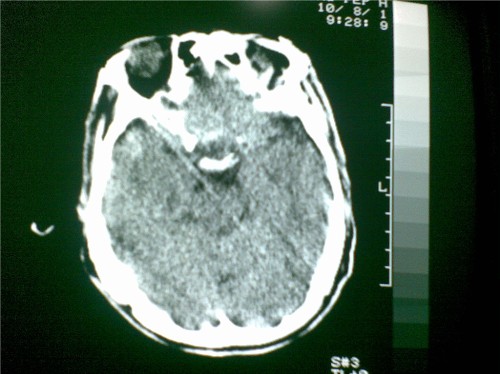

标题: CT28096:男,75岁,外伤10天后,现在恶心、呕吐。是硬膜下积 [打印本页]

标题: CT28096:男,75岁,外伤10天后,现在恶心、呕吐。是硬膜下积

硬膜下积液、右侧基底节、左侧放射冠腔梗。

硬膜下积液、多发性腔梗。

1)双侧额颞顶部硬膜下积液;建议必要时复查。2)多发性腔隙性脑梗塞。